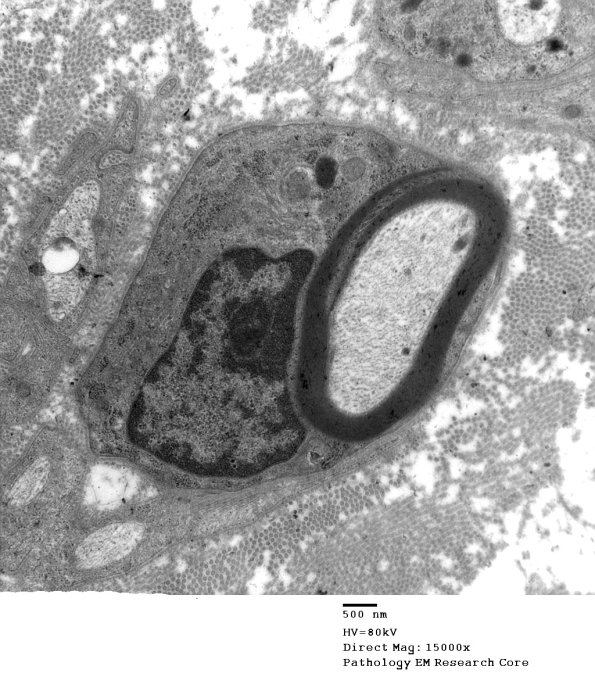

6A1-4 Multiple magnifications of this SLC originating from the external Schwann cell cytoplasm is shown. (Electron micrographs)